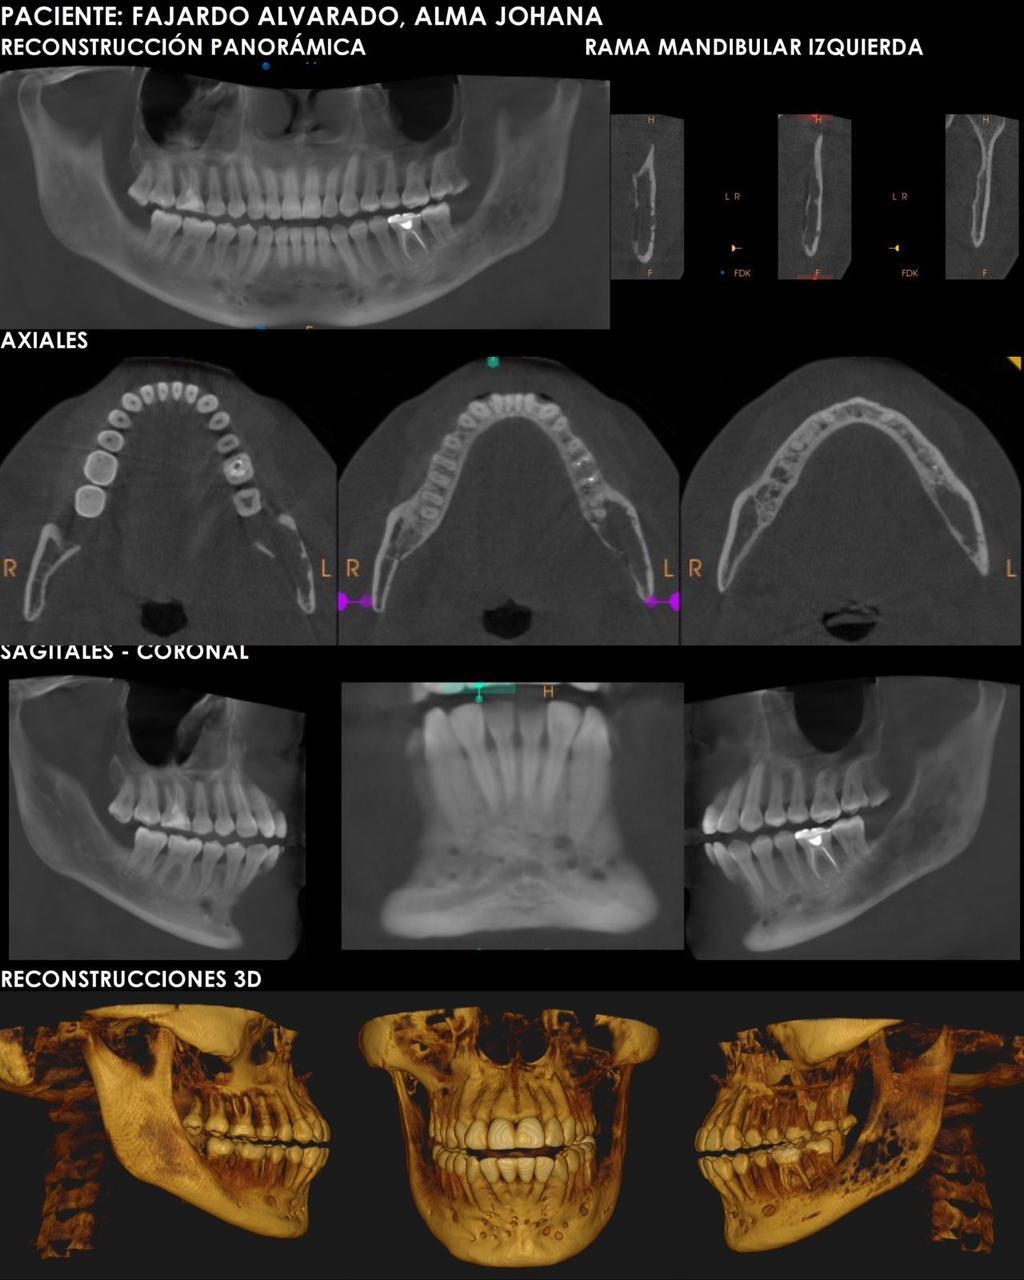

Hana, from Guatemala, lives with a rare congenital vascular condition called cervicofacial angiodysplasia. It affects her face, jaw, veins, and nerves, causing constant pain and medical uncertainty.

Hana vive en Guatemala y ha estado enfrentando, desde hace un tiempo, una condición vascular congénita poco común llamada angiodisplasia cervicofacial. Esta condición ha afectado su rostro, mandíbula, sistema venoso y nervioso. Este diagnóstico llegó acompañado de múltiples intervenciones, dolores constantes y un largo camino de incertidumbre clínica.

Las complicaciones derivadas de la malformación arteriovenosa incluyeron una cirugía de emergencia en la que casi pierde la vida tras un choque hipovolémico. En ese momento le realizaron una cervicotomía, durante la cual ligaron arterias, vena carótida externa y yugular externa. Desde entonces, ha desarrollado un dolor neuropático crónico, que aún está siendo evaluado y que afecta su calidad de vida de forma significativa.

Uno de los episodios más duros que ha tenido que atravesar fue el intento de un procedimiento de biopsia en el maxilar inferior izquierdo que terminó en complicaciones graves y provocó múltiples hemorragias severas. A raíz de esto, fue necesario realizarle un procedimiento quirúrgico intraoral llamado rotación del colgajo del carrillo, para cerrar la cavidad abierta desde donde se desangraba debido a la lesión hemorrágica. Esta intervención, sumada a todas las anteriores, dejó nuevas secuelas y más preguntas que respuestas.